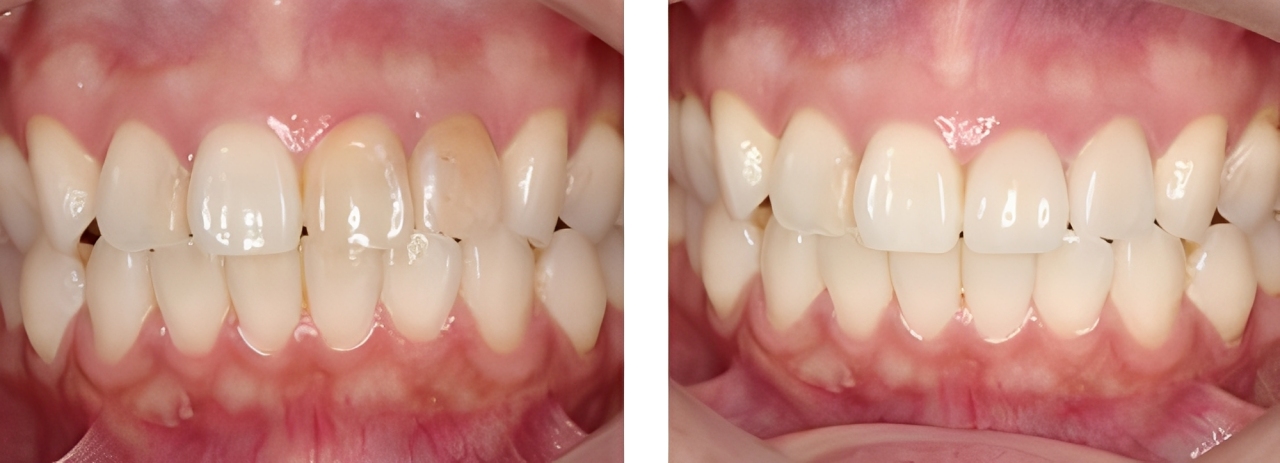

審美歯科

術前

術後

| 治療内容 | 色調・形態が左右非対称でありジルコニアセラミックにて治療を行った |

|---|---|

| 治療期間・回数 | 2カ月・6回 |

| 費用 ※自由診療となります |

プロビジョナルレストレーション:2,200円×2 ファイバーコア:16,500円 ジルコニアセラミック:132,000円 |

| リスク・副作用 |

|